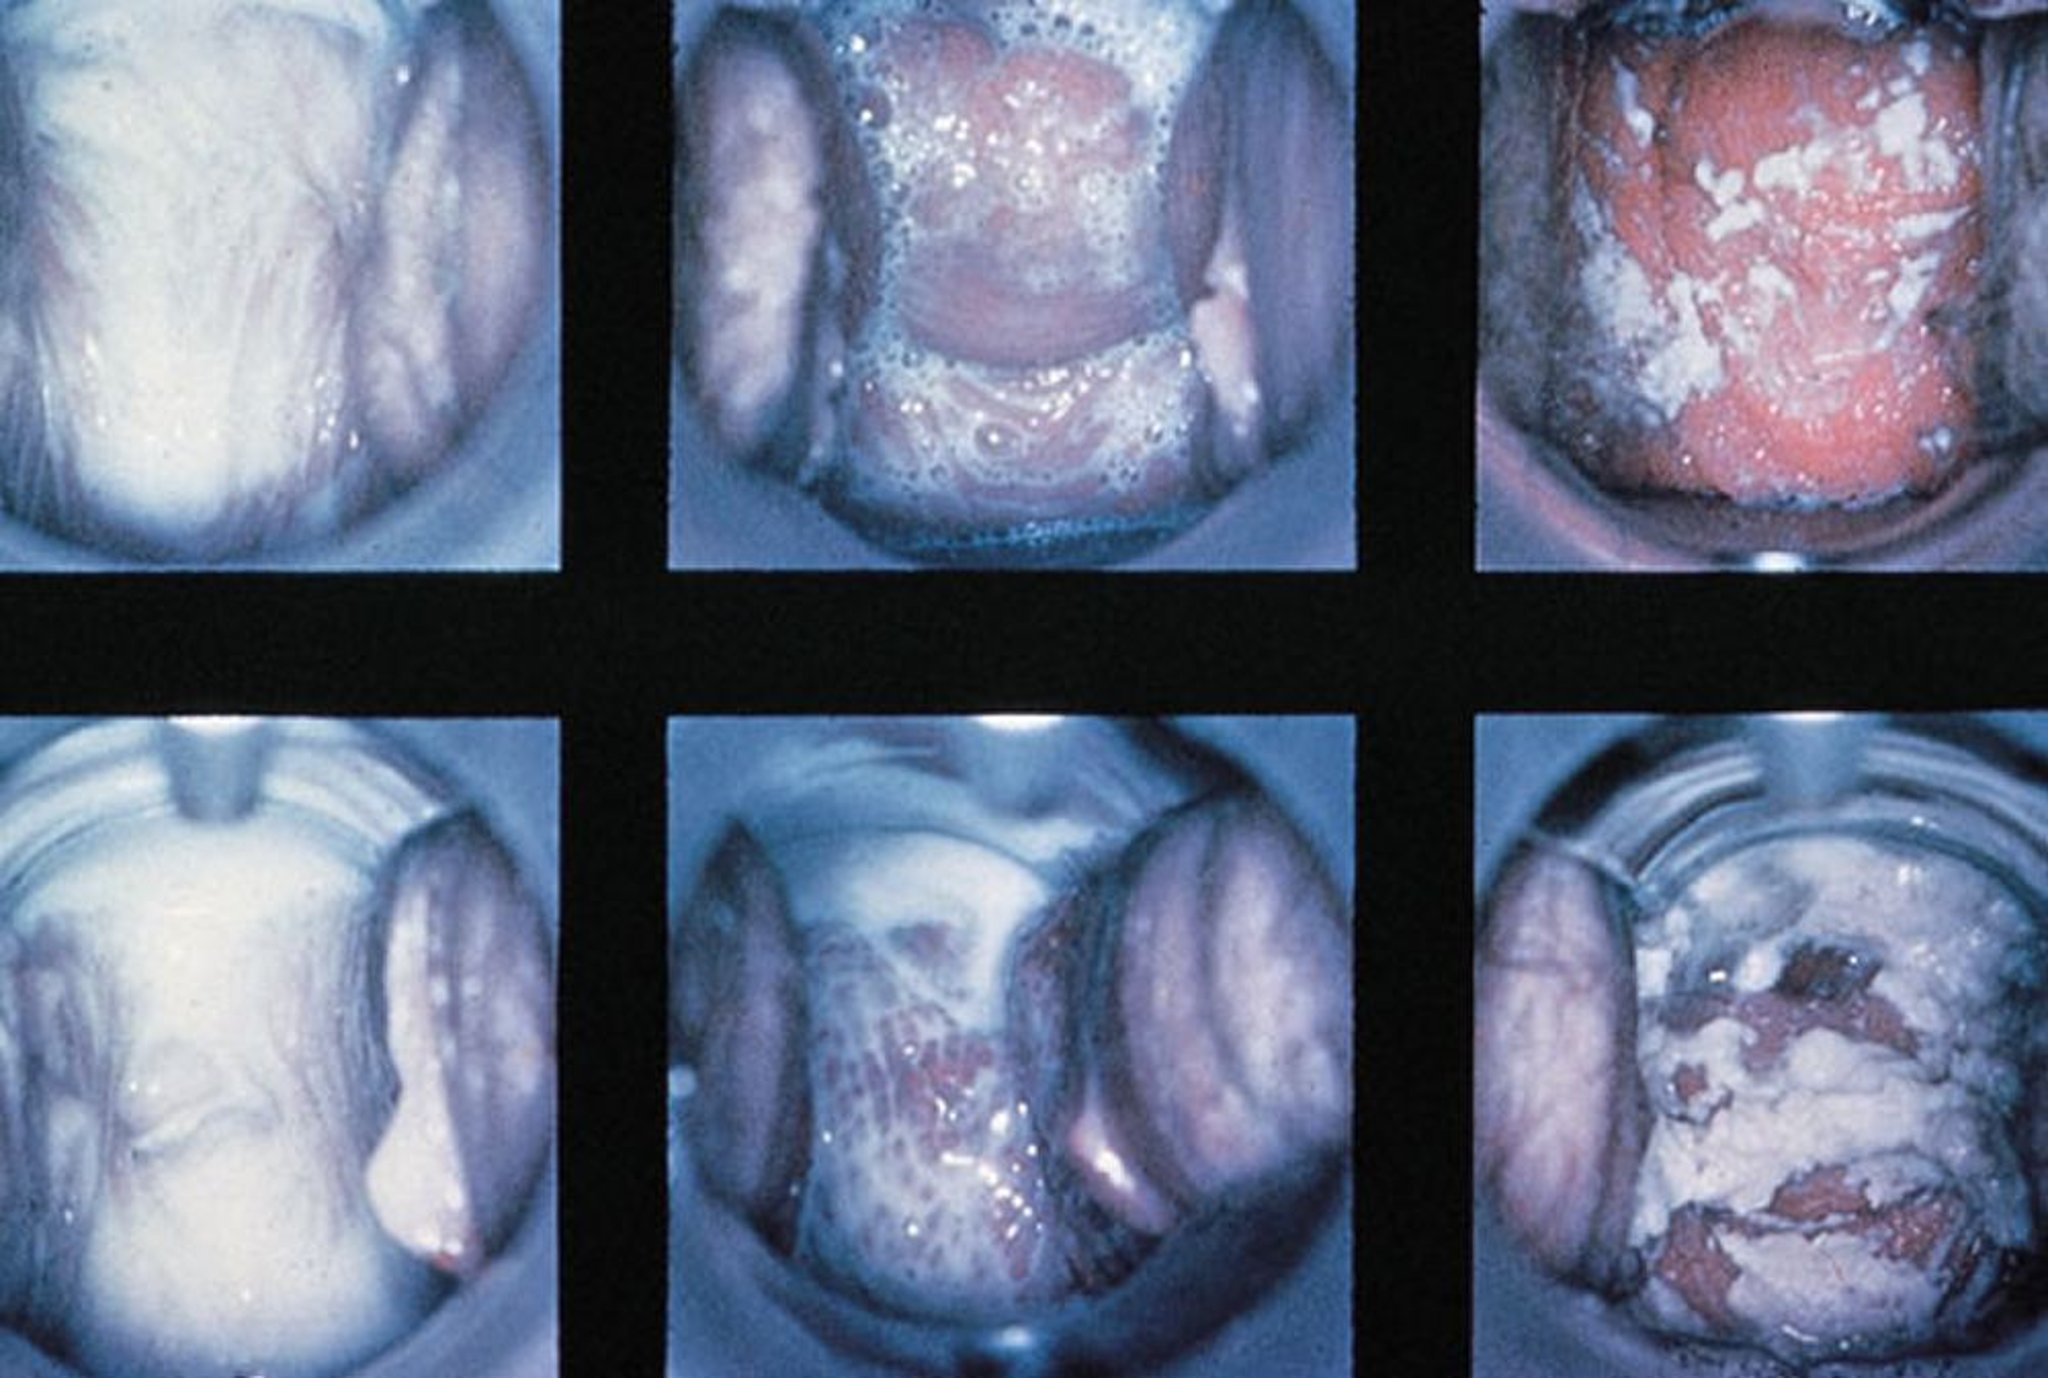

Exame especular na vaginite

Achados normais, vaginite por tricomonas com secreção espumosa e vaginite por Candida com secreção espessa e branco são mostrados (da esquerda para a direita).